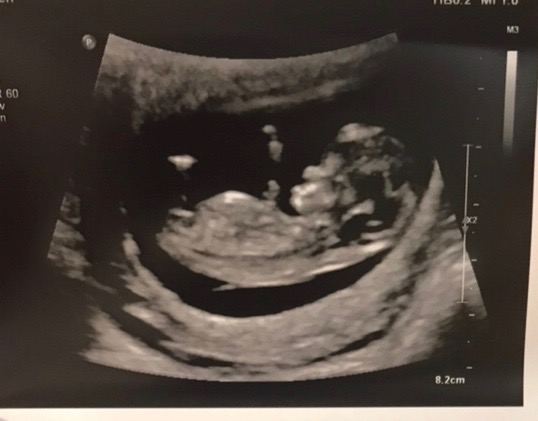

I’ll never forget my first ultrasound. Seeing our baby with such a tiny heartbeat reduced me to tears instantly. On our first ultrasound, we thought we were eight weeks, but turns out we were at six weeks! Our due date of October 14th was pushed back to the 22nd and we were in awe of how tiny our little beansprout was. There is nothing like seeing your baby for the first time: the fear, the worry, the excitement all join together in one emotion until you see that little heart beating away, then just an overwhelming feeling of joy.

The second ultrasound was taken at eleven weeks. I was shocked to see how much she/he had grown. The technician was measuring my ovaries and uterus and we got a quick glance of the baby before the big moment and she/he was dancing around! I exclaimed “Oh my God!” How could our little baby grow that fast! Of course she/he automatically tried napping when the ultrasound technician need her/him to move for the genetic scan. We tried coughing, jumping jacks, and using the ultrasound probe the jiggle the baby to move, but baby was settling in for a nap and just kept rolling over as if to say “leave me alone already!” We have one deep sleeper here, just like mama.